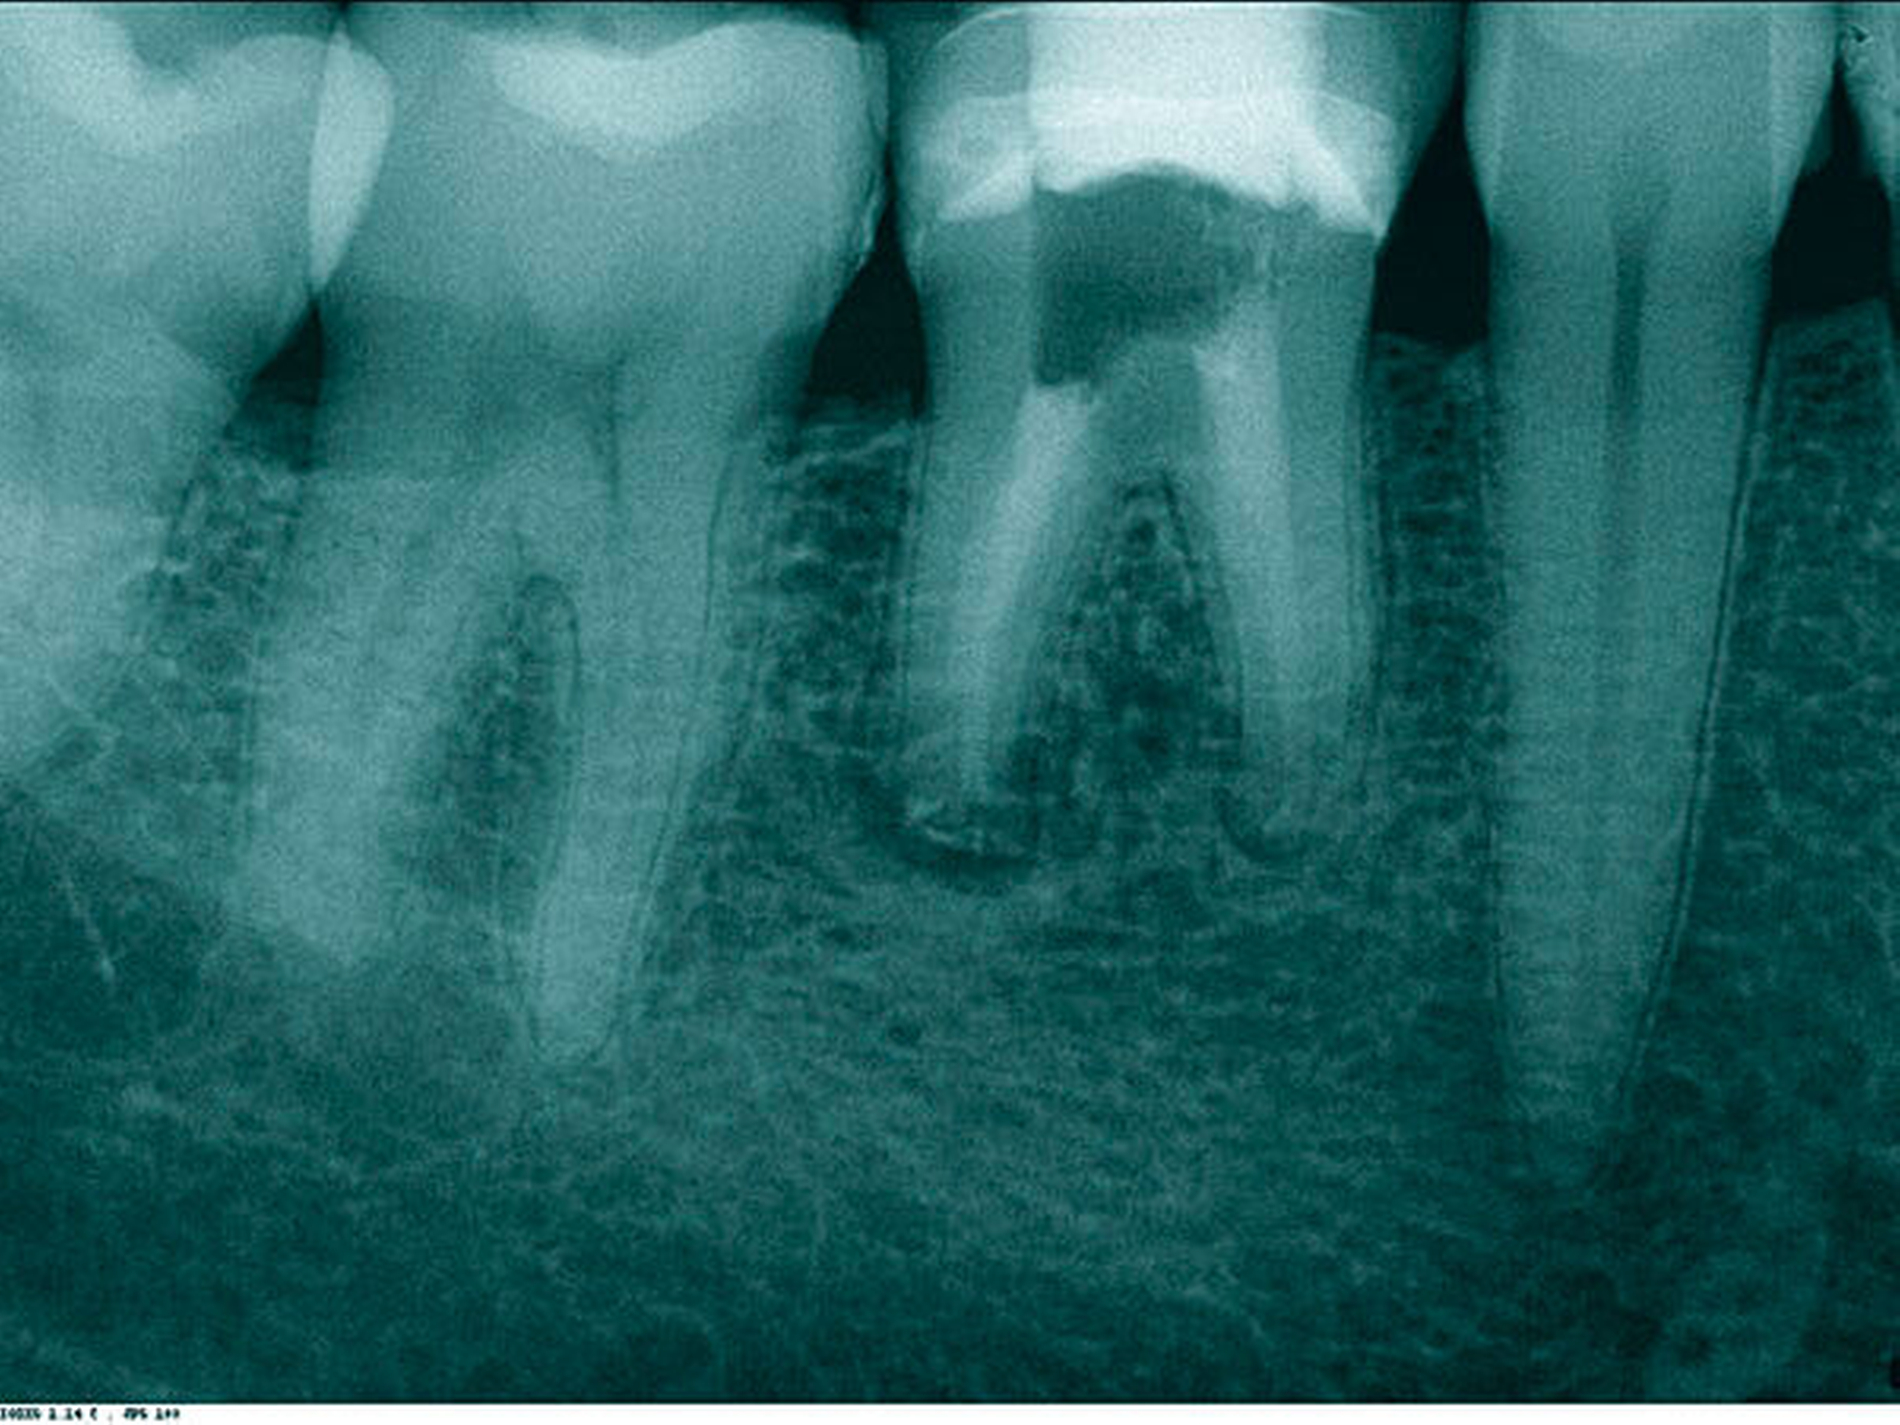

In der ersten Therapiesitzung erfolgte – nach Isolierung mit Kofferdam – die Trepanation des Zahnes und die Stiftentfernung mit Ultraschallinstrumenten. Im Anschluss wurden die drei gefüllten Kanäle revidiert, der vierte, nicht abgefüllte, mesiobukkale Kanal dargestellt und präpariert. Die elektronische Längenmessung ergab 14,5 mm für den mesiobukkalen Kanal, 17,0 mm für den mesiolingualen, 15 mm für den distobukkalen und 16 mm für den distolingualen. Aufgrund der großen initialen Kanaldurchmesser und der guten Einsicht bis ins periapikale Gewebe (Abbildung 2) wurde auf eine Längenmessaufnahme verzichtet. Die Desinfektion erfolgte mit Natriumhypochlorid (NaOCl) 5 Prozent und EDTA 17 Prozent, sowie Schallaktivierung mittels EDDY-Spitzen (VDW, München). Das Wurzelkanalsystems wurde manuell mit K-Feilen bis IS0 70 präpariert. Es folgte eine medikamentöse Einlage mit AH Temp (DentsplySirona, Bensheim). Danach wurde eine Aufnahme zur Kontrolle der vollständigen Guttapercha-Entfernung und der suffizienten Einbringtiefe des Kalziumhydroxids angefertigt (Abbildung 3).

Bereits nach der ersten Sitzung war der Patient symptomfrei. In der zweiten Sitzung wurden nach erneuter ausgiebiger Reinigung und Desinfektion des Kanalsystems in allen vier Wurzelkanälen apikale Plugs mit Total Fill BC Root Repair Material (FKG, La Chaux-de-Fonds, Schweiz) appliziert (Abbildungen 4 und 5) und es wurde eine Röntgenaufnahme zur Kontrolle der Plugs angefertigt (Abbildung 6). Anschließend wurden die restlichen Kanalanteile mit Total Fill BC Sealer und warmer-vertikaler Fülltechnik abgefüllt, der Zahn wurde adhäsiv verschlossen und ein Röntgenkontrollbild angefertigt (Abbildung 7). Bei der Verlaufskontrolle nach sechs Monaten war radiologisch bereits ein deutlicher Rückgang der Läsion zu erkennen (Abbildung 8), der Patient war nach wie vor symptomfrei.